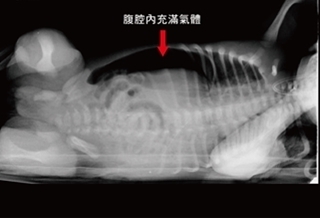

腹部氣脹 出生2天竟胃穿孔

腹部氣脹 出生2天竟胃穿孔#消化系統

(優活健康網記者徐平/綜合報導)一名出生才2天的男嬰,因先天性血管不良,導致胃缺血缺氧而局部壞死穿孔,到院時心跳加快、呼吸急促、全身性蒼白,經X光檢查,發現腹腔內充滿氣體,醫師判斷消化系統有破洞,在切除約4/5的胃後,已經可以正常喝奶,體重也增加500公克。血壓偏低、發炎指數偏高、哭聲弱澄清醫院新生兒加護病房主任黃元韻表示,該男嬰到院時的血液循環不是很好,血壓偏低、發炎指數也偏高,出現全身性蒼白且哭聲無力微弱,腹部氣脹,必須由小兒外科緊急開刀,否則會有生命危險。澄清醫院小兒外科主任林雨利指出,男嬰腹腔中滿佈黃色的結塊,且胃部組織已破了一個洞,男嬰已呈現敗血症現象,清理出黃色結塊並將胃部切除約4/5後,才救回小嬰兒一命。胃患部薄弱 乳液脹破胃壁流到腹腔林雨利主任解釋,腹腔內的黃色結塊是嬰兒餵食奶水後與胃酸綜合後,從胃部的破洞流出,由於該男嬰先天性供給胃部的血管不良,在母胎中其胃尚未運作,一出生後胃就開始運作,有可能在缺血缺氧的胃患部已呈薄弱現象,當一開始餵乳後,乳液就脹破單薄處的胃壁,流到腹腔裡。該男嬰手術成功後,術後的照顧就交給新生兒加護病房醫護人員,黃元韻主任表示,一開始以全靜脈營養照護該男嬰,7天後再從水到奶水餵食,經住院一個月,該男嬰由原本的3000公克體重增加至3500公克而順利出院,目前該男嬰每3小時的食量已達100西西的奶水,身體健康。注意營養均衡、少量多餐黃元韻主任指出,像這樣出生2天就胃部切除4/5的嬰兒,基本上要注意營養均衡,最好的方法是少量多餐,隨著男嬰長大,胃部會再擴大,吃固體食物仍需多加注意,並且需定期回診。